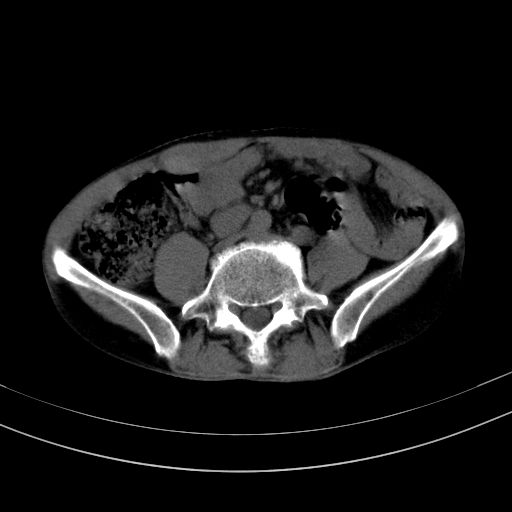

以下是引用37度在2010-1-9 14:37:00的发言:[br]1.双肾囊肿,左肾积水结石,.胆总管轻度扩张;[br]2.病灶在腹膜外,考虑纤维瘤。

以下是引用dyqct在2010-1-9 17:56:00的发言:[br]考虑:1.双肾囊肿,左肾积水结石、旋转不良。[br] 2.右侧腹直肌血肿或纤维瘤。[br]肠道准备不好。做个增强。